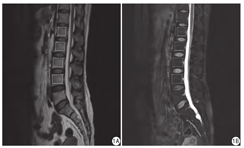

在图像储存与传输系统工作站上,找到纳入病例的腰椎MRI图像,由前期熟练掌握测量方法的2名医师共同阅片,综合王明明等[4]及翁子敬等[5]的测量方法,选择矢状位T2WI及FS-T2WI序列图像中经过L1~4椎体正中层面图像,手工绘制ROI,ROI要最大范围地包括整个椎体的松质骨部分,避开骨皮质及椎间盘,并尽量保证T2WI及FS-T2WI序列ROI一致的情况下,分别测量L1~4椎体在两序列上的信号强度值(signal intensity,SI),计算各椎体SI差值的均值,即SI差值=(SIT2WISIFS-T2WI)/4。

88例纳入病例按照DXA骨密度结果分组情况为:正常组43例,骨质减少组14例,骨质疏松组31例。腰椎SI值测量方法如图1。按图1所示测量方法,各组信号差值分别为:正常组103.95±34.08,骨质减少组193.46±38.35,骨质疏松组206.80±34.72,骨质异常组为202.65±35.99。正常组、骨质减少组、骨质疏松组三组间差异有统计学意义(F=88.19,P<0.01),骨质减少组与正常组间差异有统计学意义(P< 0.01),骨质疏松组与正常组间差异有统计学意义(P<0.01),骨质减少组与骨质疏松组间差异无统计学意义(P=0.24) ;正常组与骨质异常组间差异有统计学意义(P<0.01)。SI差值=156.15时,区分骨质正常与骨质异常曲线下面积最大,为0.983,敏感度和特异度分别为93.3%、93.0% (图2)。